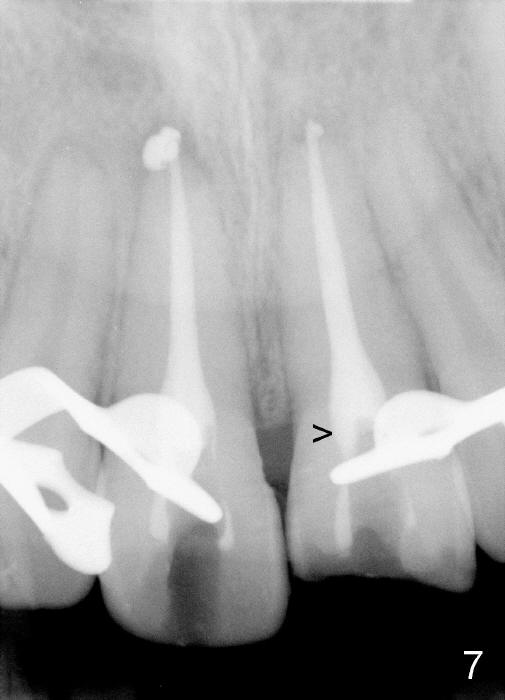

The patient returned to finish RCT 1.5 months later (Fig.6). Gutta percha was removed as much (high) as possible (Fig.7 >). In order to prevent butterfly rubber dam clamp interference in access and GP removal, smaller clamps should be placed in the neighboring teeth (Fig.8). When RCT was done, the tooth #9 was still the darkest (Fig.9). Thermoplastic tab was used to make local external bleaching tray (Fig.10 *). The patient and his mother were instructed to do external and internal bleaching daily.